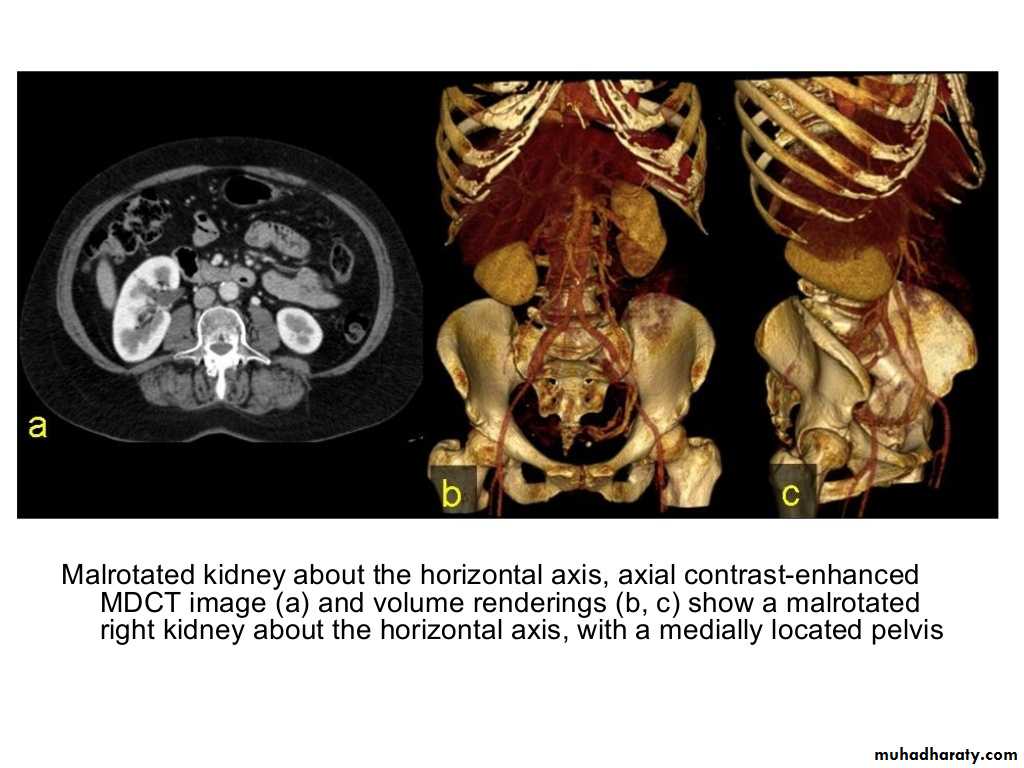

IVU shows

1. The kidneys at low position .2.Close to the spine with long axis parallel to the spine

3. Malrotation manifested by medially directed calyces.

4- The renal pelvis and ureters are anterior and lateral in position.

5- Hydronephrosis and calculi highly associated.